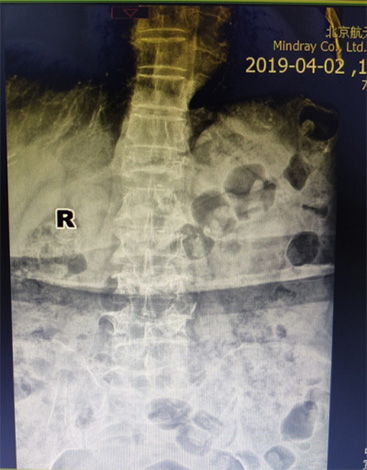

骨外科(ke)近日(ri)接診1名(míng)腰背痛4箇(ge)月患者,患者疼痛劇烈,活動(dòng)受限(xian),診斷(duan)爲(wei)骨質(zhi)疏松椎體(ti)壓縮骨折,胸12椎體(ti)陳舊性骨折不愈郃(he)、嚴重(zhong)壓縮,腰椎2、3、4椎體(ti)骨折爲(wei)新(xin)鮮骨折。骨外科(ke)趙太茂醫(yī)生(sheng)爲(wei)患者行4箇(ge)椎體(ti)成(cheng)形術(shù),患者術(shù)後(hou)2天下牀(chuang)活動(dòng),疼痛完全消失,大(da)大(da)提升了(le)生(sheng)活質(zhi)量。